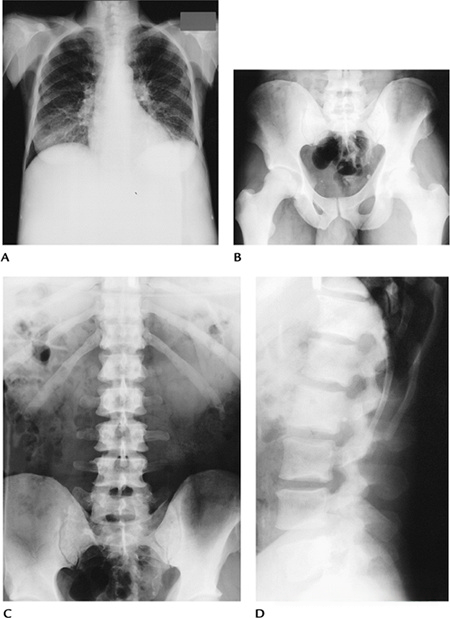

7a1720be8baf1259e6575c4ff03a3773.png

图-13  75岁男性因使用糖皮质激素导致的骨质疏松。(A)矢状位T2显示椎体压缩,信号减低和增高混合。(B)SE-DWI显示一个高信号区(箭头),这是由肺部转移引起的。

fba59273f7a0d4393edd5a753f4207d2.png

(A) 六个月前,胸椎矢状位 T2 加权 MRI 显示 T9 和 T12 急性压缩性骨折。

(B) 椎体后凸成形术后,腰椎矢状位 T2 MRI 显示 T8 、 T10 和 T11 处急性压缩性骨折,T9和 T12 处有明显的骨折线。

78d7497994d97e7d84a7cea36831d930.png

(A) 脊柱矢状脂肪抑制增强 T2 MRI 显示 T8、9、10 脊柱炎伴左侧椎旁和前韧带下脓肿(箭头)以及 T8 至 L5 的压缩性骨折。